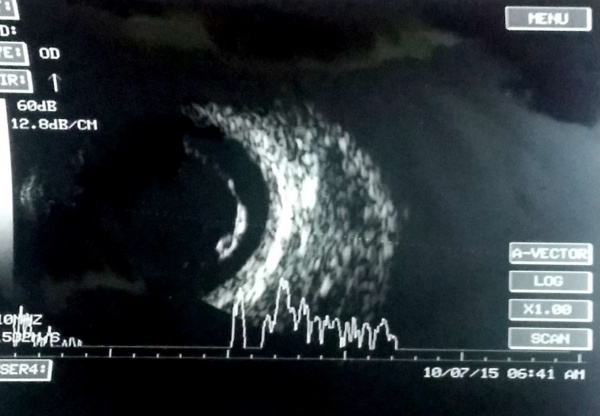

Ultrasonography of Choroidal hemangioma

It is solid dome shaped mass of choroid with high amplitude (and thickening of the choroid) but no angle kappa (sound attenuation) unlike choroidal melanoma. The lesions are usually mildly elevated (height is less than width), unlike the melanoma which may have height more than width.